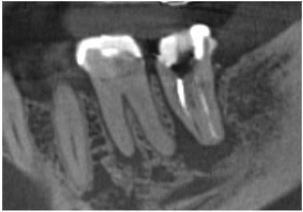

根管治療

精密根管治療

Before

After

| 主訴 | 左下の奥歯に違和感がある |

|---|---|

| 診断名 | 左下第二大臼歯の慢性根尖性歯周炎 |

| 年齢・性別 | 40代、女性 |

| 治療期間・回数 | 6回、2ヶ月 |

| 治療方法 | 精密根管治療 |

| 備考 | 当院では、歯を残すために保険診療でもマイクロスコープを使用することがあります。 歯科的既往歴:一年前、他の歯科医院にて下顎両側大臼歯の被せ物の治療を受けた。その後から左側第2大臼歯の違和感がある。 前主治医に違和感を訴えたが、噛み締めから来てると言われ、マウスピースを作成し、様子を見るよう指導された。その後も違和感や痛みは治まってない。 |